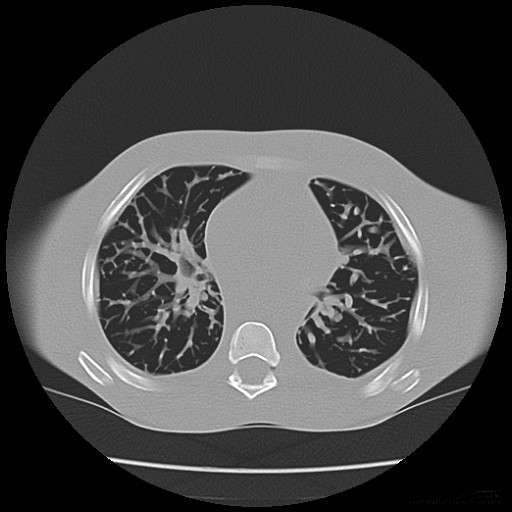

灰度图像CT.JPG

阈值分割得到肺实质

subplot(241);imshow(I),title('原始图像'); %显示图像